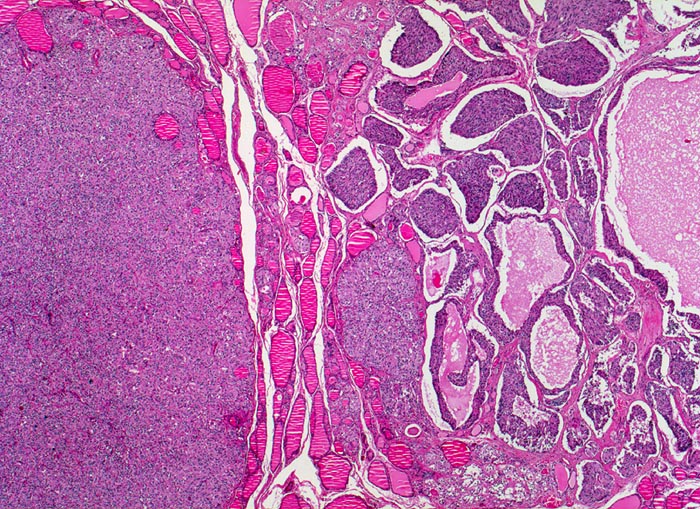

• Die Tumorinfiltrate bestehen aus soliden und kribriformen Verbänden spindeliger Tumorzellen.

• Mehrere Herde hyperplastischer C-Zellen im nicht-neoplastischen Schilddrüsenparenchym als möglicher Hinweis auf ein hereditäres medulläres Schilddrüsenkarzinom.

• Kleiner Lymphknoten mit Metastase des medullären Schilddrüsenkarzinoms. Das sollte der Kliniker dem Pathologen mitteilen: